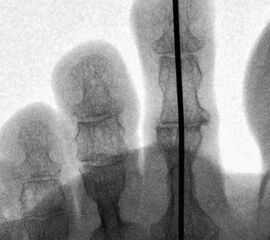

Eine relativ neue Entwicklung stellt die Verwendung spezieller intramedullärer Implantate dar. Mittlerweile sind eine Vielzahl unterschiedliche Systeme auf dem Markt. Ein wichtiges Unterscheidungsmerkmale ist die Art der Verankerung im Knochen. Dabei kann zwischen Systemen die eingeschraubt werden und Press-fit-Systemen, teilweise unter Verwendung von Formgedächtnislegierungen, unterschieden werden. Zudem wird zwischen einteiligen und zweiteiligen Systemen unterschieden. Bei zweiteiligen Systemen werden beide Komponenten getrennt implantiert und danach ineinander gesteckt.

• Eine Röntgenkontrolle wird 6 Wochen postoperativ durchgeführt (Fuß belastet in zwei Ebenen). Besonders geachtet wird auf eine knöcherne Konsolidierung der Arthrodese und auf die Lage eines gegebenenfalls verwendeten intramedullären Implantats.

Bezüglich der Verwendung von intramedullären Implantaten liegen nur wenige Berichte in der Literatur vor. Ellington et al. beschreiben eine knöcherne Fusionsrate von 60% beim Gebrauch des Stay-fuse Implantats (Tornier, Minneapolis, Minn., USA) bei insgesamt 38 korrigierten Zehen. Eine persistierende Fehlstellung in sagittaler oder coronaler Ebene trat in 18% der Fälle auf. Ein Revisionseingriff war bei drei Patienten erforderlich. Die Autoren schlussfolgern,  dass das Implantat die Korrektur ausreichend stabilisiert, obwohl die Fusionsrate vergleichbar ist mit der bei der Verwendung eines K-Drahtes zur Stabilisierung 8.  Roukis berichtet über klinische und radiologische Ergebnisse nach Benutzung des Smart Toe Implantates zu Arthrodese des PIP-Gelenks (Stryker, Kalamazoo, Mich., USA) Dabei wurde eine Fusionsrate von 93% sowie eine Malunion-Rate von 7% bei 30 Zehenkorrekturen ermittelt 9. In einer anderen retrospektiven, vergleichenden Studie von Angirasa, werden die Ergebnisse der PIP-Arthrodese unter Verwendung von K-Drähten mit dem Gerbrauch von SmartToe® Implantates (Stryker, Kalamazoo, Mich., USA) verglichen. In dieser Studie ergeben sich Vorteile für die Verwendung des intramedullären Implantates in Bezug auf Schmerzsymptomatik, Komplikationen, Rate der erreichten Arthrodese, und Zeitperiode bis zur Wiederaufnahme der Arbeit 10.